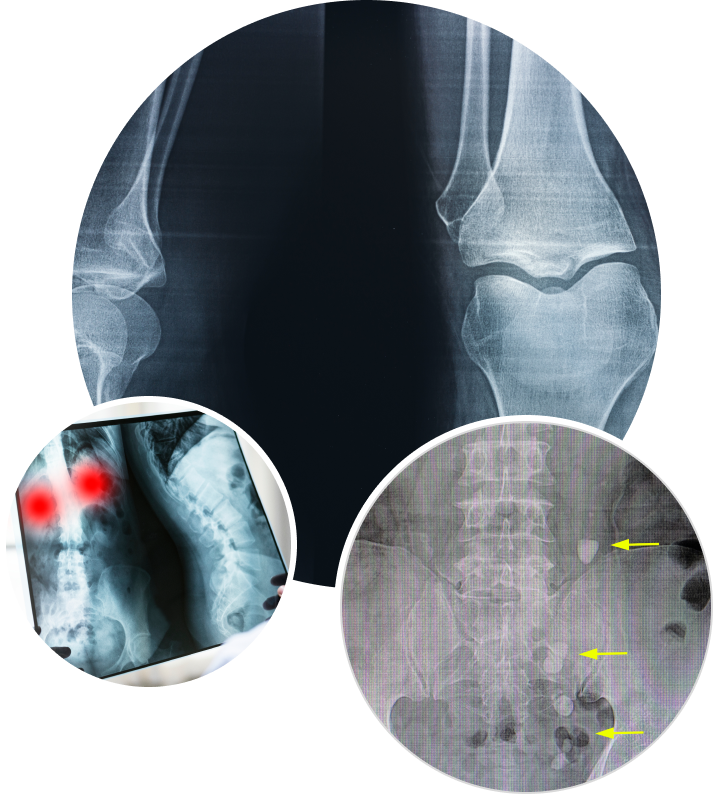

There is currently no non-invasive tool available to perform a structural and functional (as opposed to dimensional) assessment of abdominal aortic aneurysms. All currently available imaging tools provide dimensional information of the aorta only which results in a crude approximation for the surgeon on when to intervene.

ViTAA’s RAW™ (Regional Areas of Weakness) Mapping technology can analyze the deformation of the aorta wall using images captured throughout the cardiac cycle. Then, by incorporating critical simulation data on blood flow and location and size of clots (ILT or intraluminal thrombus) within the aneurysm, ViTAA’s algorithms compute and generate detailed strength and weakness maps of the abdominal aortic aneurysm.